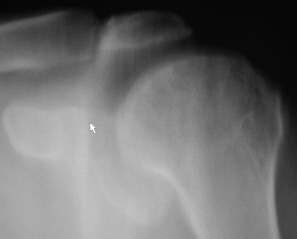

Иллюстрация 1 и 2. Рентгенограмма и фрагмент рентгенограммы с увеличением. В области головки плечевой кости определяются нерезко очерченные участки намечающегося остеопороза. Визуализируется нечеткость контура головки плечевой кости по латеральному контуру, в области большого бугорка. Определяется перестройка структуры костной ткани в области дистального отдела акромиального отростка лопатки. По верхнему краю определяется неровность и нечеткость контура. Решено произвести томографическое исследование.